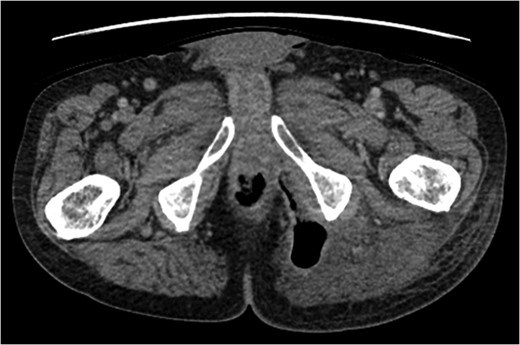

A rare complication of diverticular disease is the formation of fistulas, most commonly either colo-vesical or colo-vaginal. We present the unusual case of a perforated sigmoid diverticulum forming a colo-gluteal fistula and presenting initially as a gluteal abscess in an otherwise asymptomatic patient. After drainage of the gluteal abscess, the patient re-presented with faecal loss from the abscess drainage site. Imaging revealed fistulous communication between the sigmoid and the left obturator internus muscle, tracking to the gluteus maximus with associated abscess and cutaneous communication to the site of previous drainage. The patient underwent an emergency Hartmann's procedure with lay open/abscess drainage of the gluteal cavity. Post-operatively the patient experienced continuing discharge from the gluteal fistula despite repeated drainage and debridement causing considerable morbidity, inconvenience and misery. Clinicians should maintain a high index of suspicion when presented with a gluteal abscess and should consider the possibility of an intra-abdominal source.

The patient re-presented a week after discharge, complaining off persistent pain around the buttock, with feculent discharge and flatulence from the wound. Abscess cultures from the previous admission were reviewed and noted to have grown Escherichia coli and clostridium species.

An emergency Hartmann's procedure was performed under general anaesthetic through a lower midline incision as well as lay open of the perineal fistula. On opening the abdomen, a perforated diverticulum was identified extending into the left lateral pelvic wall. A standard Hartmann's procedure was performed, with sigmoid colectomy, division of rectum at recto-sigmoid junction and a tension-free stoma formed in left hypochondrium. The left buttock abscess cavity extended by a further 2–3 in. and the cavity then packed.